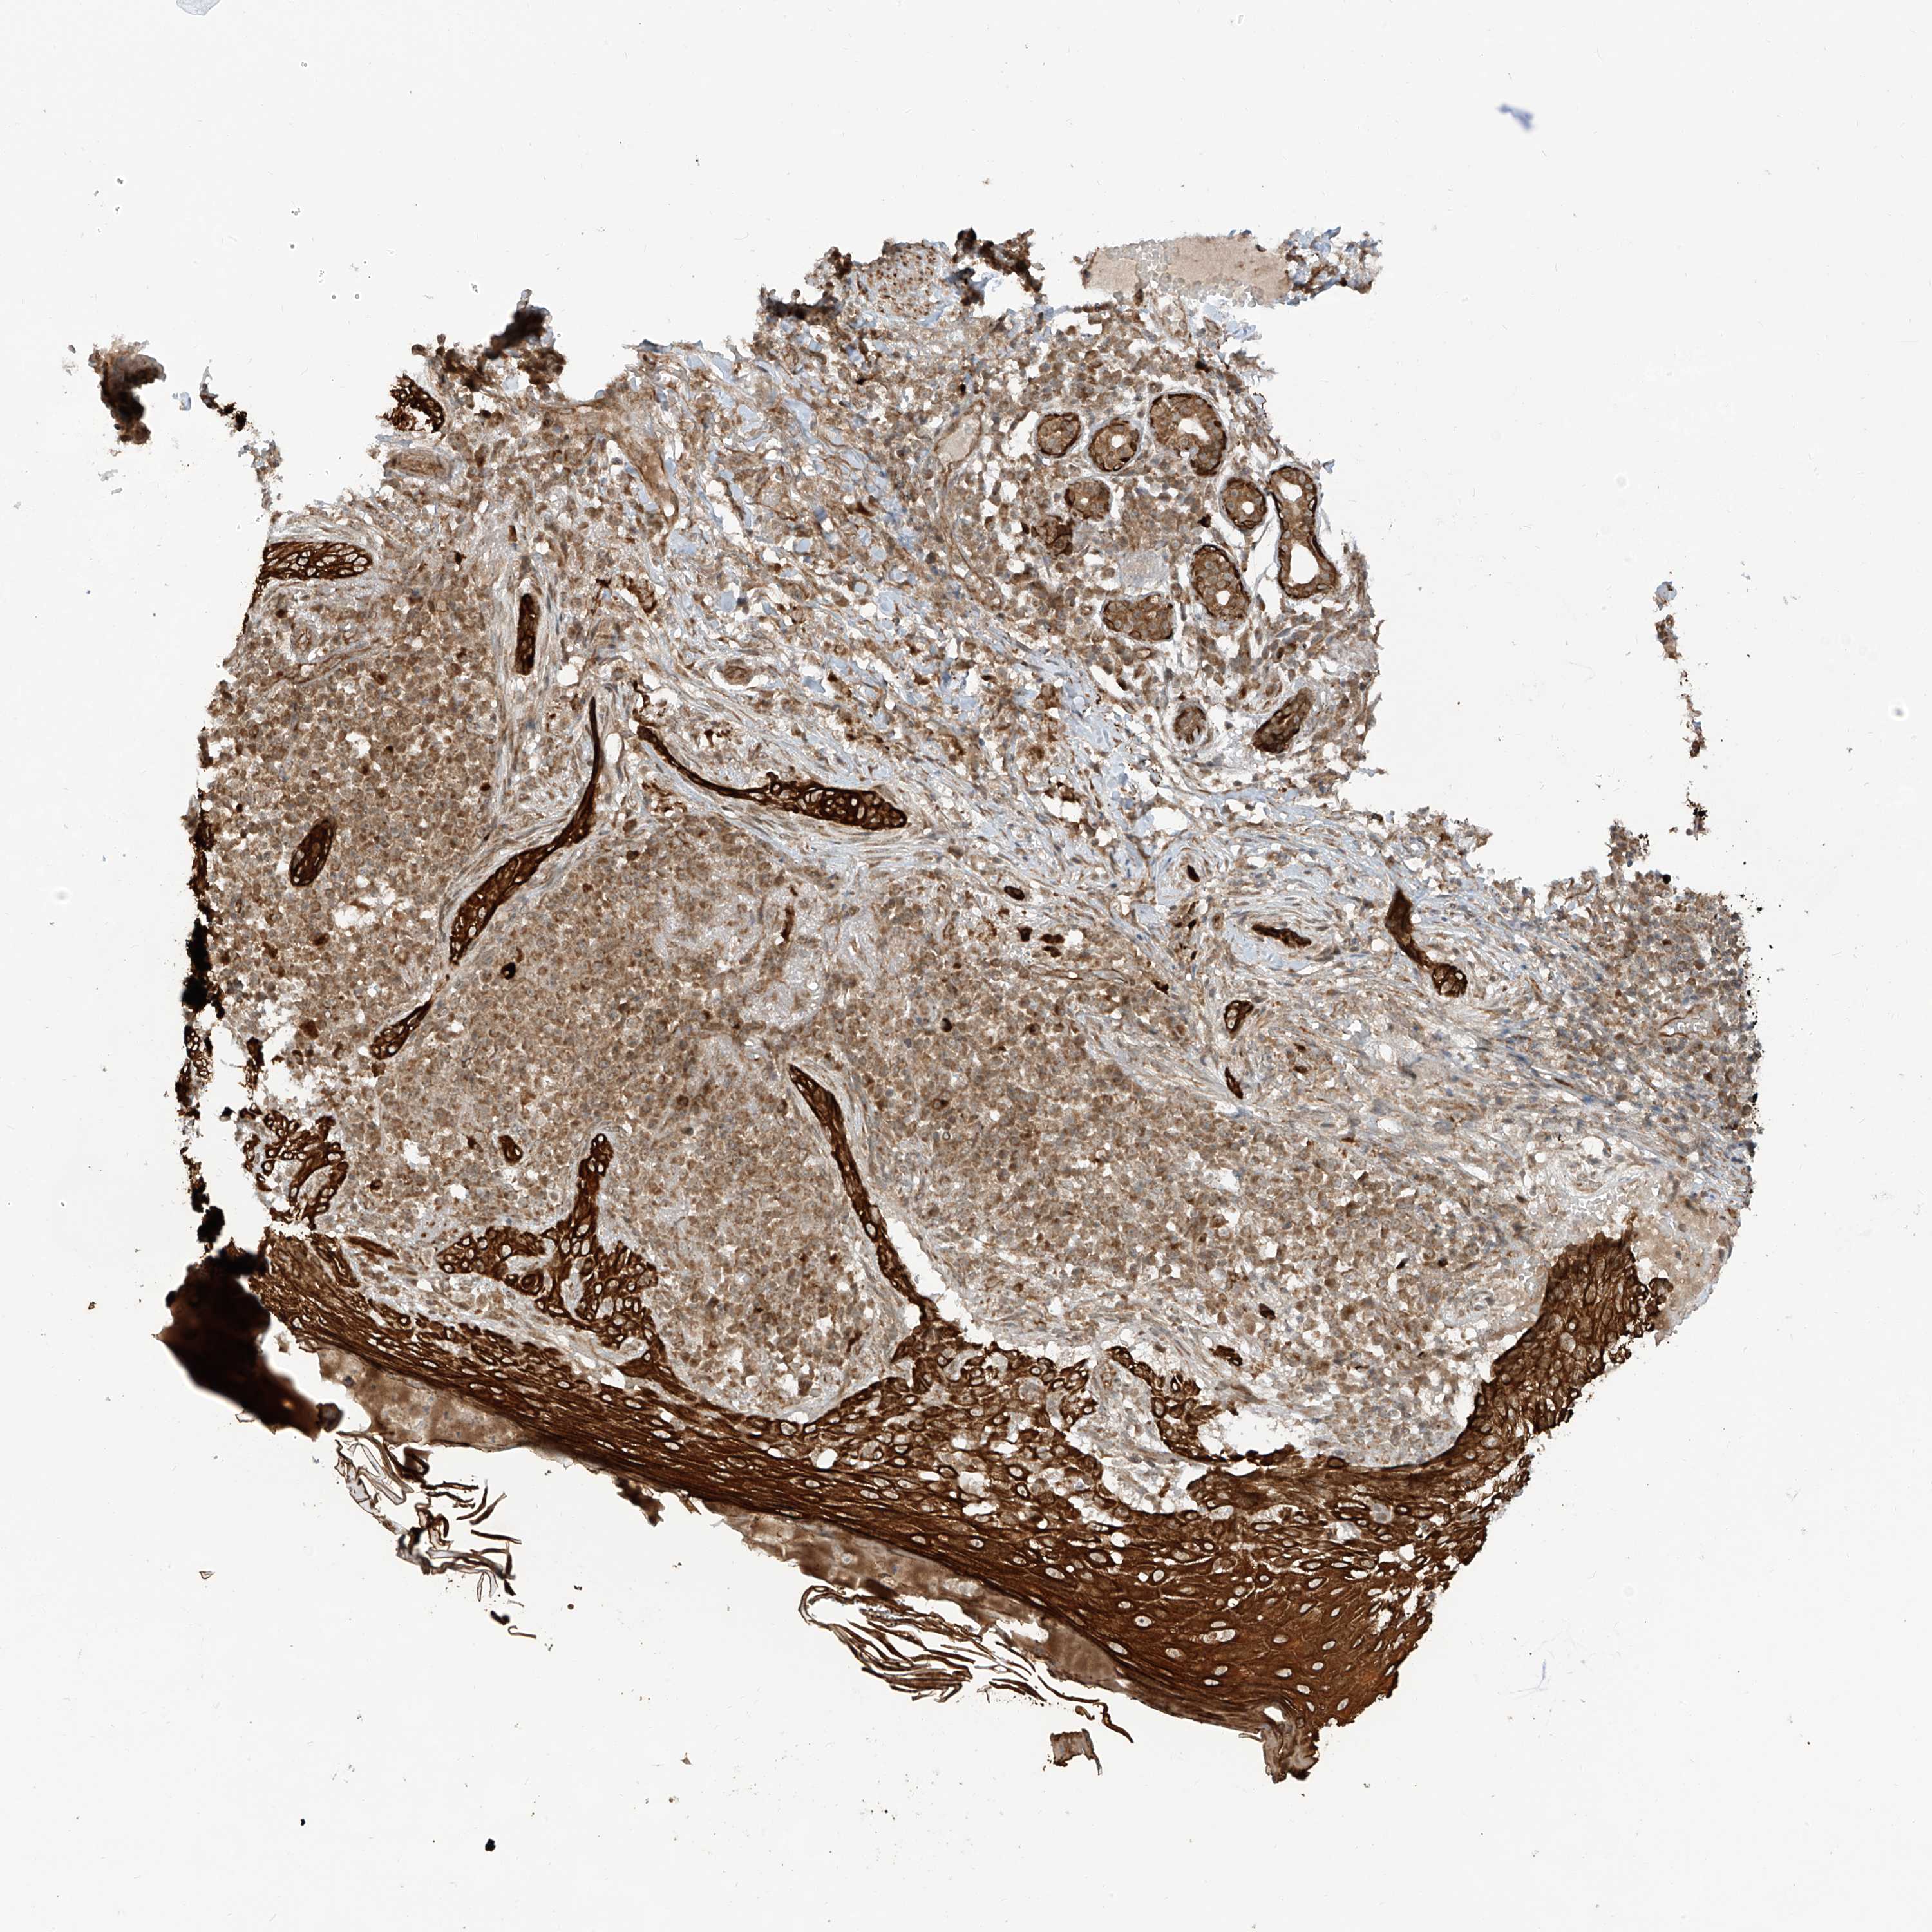

SKIN CANCER - Protein expressioni

A mouse-over function shows sample information and annotation data. Click on an image to view it in a full screen mode. Samples can be filtered based on level of antibody staining by selecting one or several of the following categories: high, medium, low and not detected. The assay and annotation is described here.

Antibody stainingi

Antibody staining in the annotated cell types in the current human tissue is reported as not detected, low, medium, or high, based on conventional immunohistochemistry profiling in selected tissues. This score is based on the combination of the staining intensity and fraction of stained cells.

Each image is clickable and will lead to virtual microscopy that enables deeper exploration of all samples and also displays staining intensity scores, fraction scores and subcellular localization as well as patient and tissue information for each sample.

Antibody HPA034776

Staining

High

Medium

Low

Not detected

Intensity

Strong

Moderate

Weak

Negative

Quantity

>75%

75%-25%

<25%

None

Location

Nuclear

Cytoplasmic/membranous

Cytoplasmic/membranous,nuclear

Basal cell carcinoma

Squamous cell carcinoma, NOS

Squamous cell carcinoma, metastatic, NOS